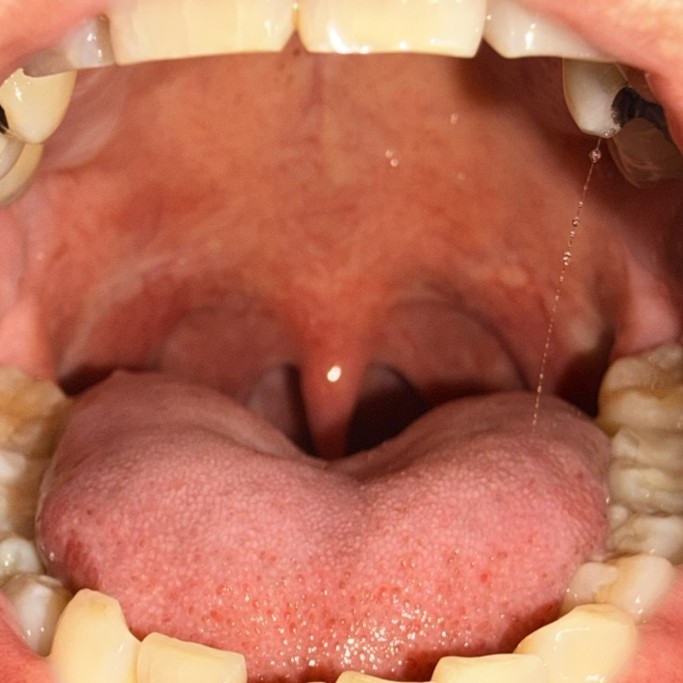

症例1 施術後1カ月経過